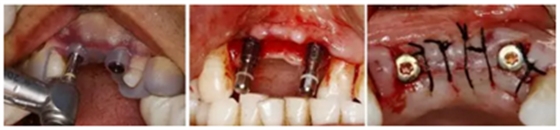

(1)拔牙后PRF復(fù)合GBR技術(shù)行位點(diǎn)保存

(2)數(shù)字化3D種植外科導(dǎo)板的設(shè)計(jì)制作

(3)數(shù)字化3D種植外科導(dǎo)板引導(dǎo)下Straumann 3.3x12 NC 種植體行延期種植